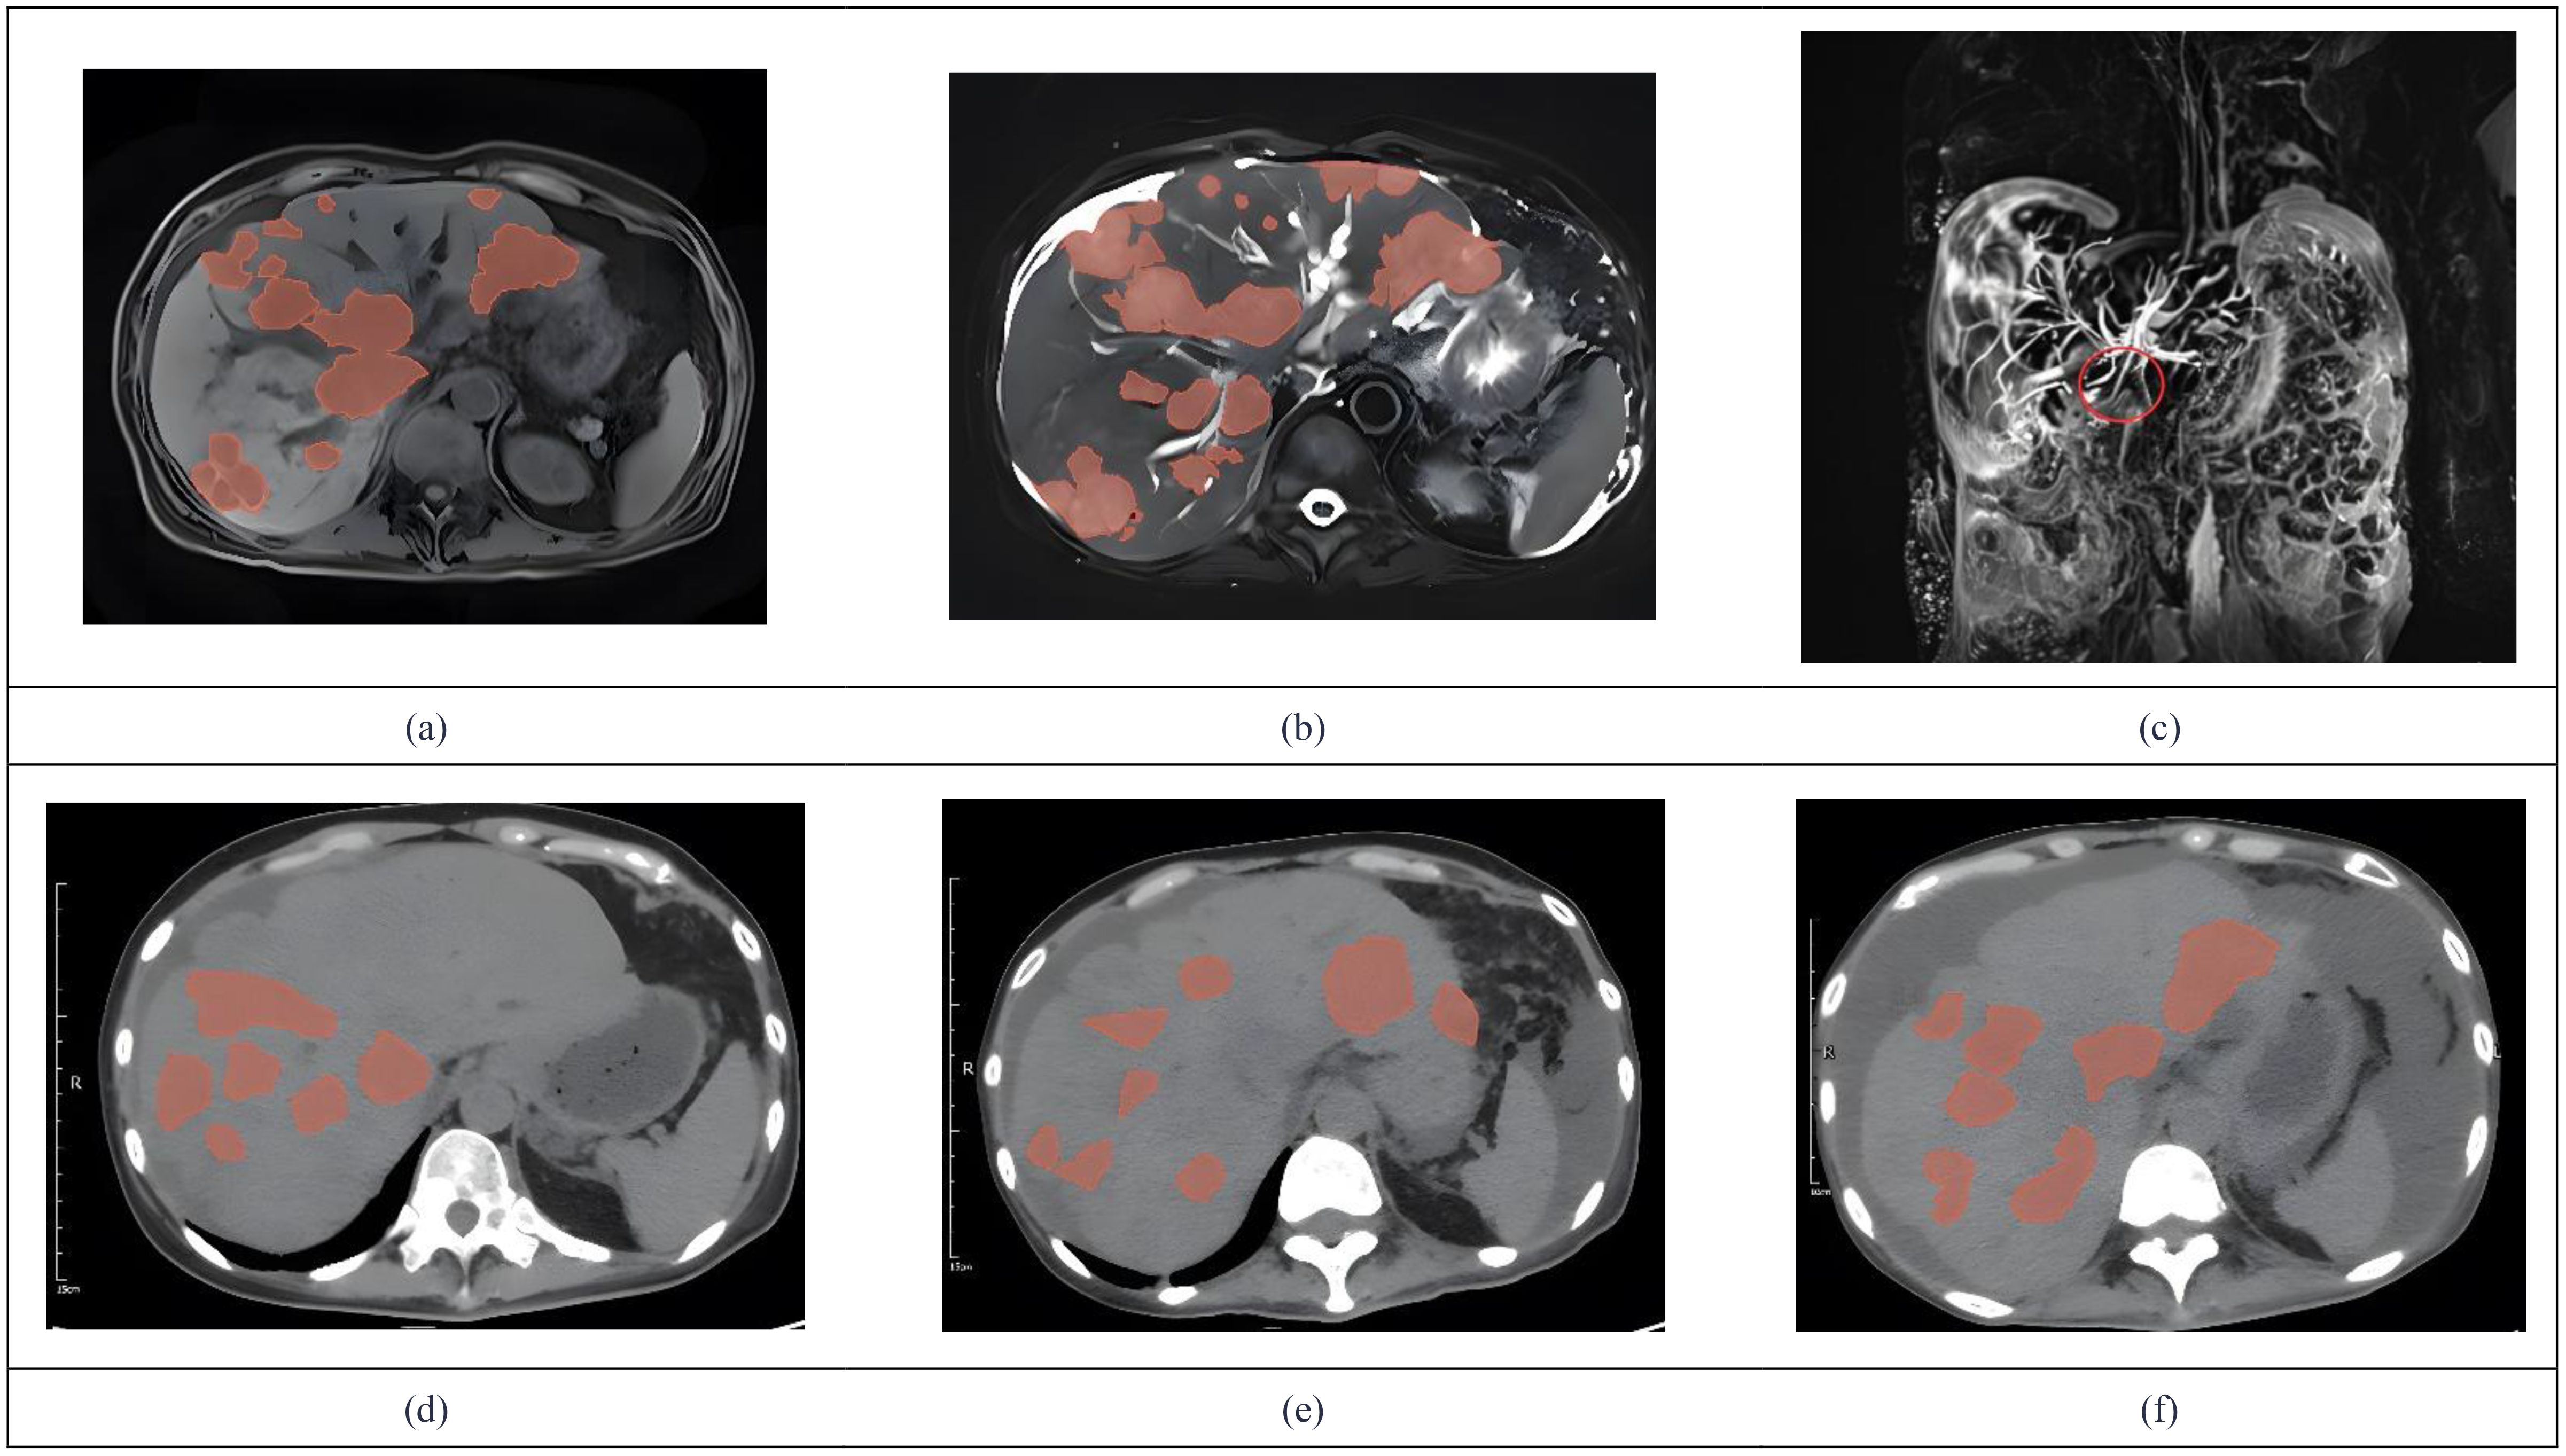

In 2024, a 45kg female patient who was admitted due to fatigue, anorexia, and dark yellow urine for 4 months. Her abdominal distension occurred 4 months ago, and then developed fatigue, loss of appetite, dark yellow urine, and mild abnormal liver function, but she did not take any medical treatment, and these symptoms became worsen in 5 days. 6 years before, she was diagnosed with breast cancer and received surgically resected, multiple rounds of radiotherapy, chemotherapy, and targeted therapy. 4 months before, she was monitored with recurrence of breast cancer and distant metastasis to brain and bones, and begun cranial radiotherapy, meanwhile, the systemic therapies, including targeted therapy, were discontinued. The patient concurrently begun a regimen of anti-tumor Chinese herbal decoctions. She has no family history of liver disease. Physical examination: we found her with severe jaundice of the skin and mucous membranes, and liver palms, and the swelling liver exceeded the right xiphoid 3cm, with a hard texture. Laboratory tests: autoimmune antibodies and serum markers of hepatitis virus were negative. Chest computerized tomography (CT) scan showed multiple small nodules in both lungs, local atelectasis in the right middle lobe and left lower lobe, and postoperative changes were consistent with the loss of the left breast (Figure 1). Suspicious nodules can be seen in some vertebrae, which require further examination. Abdominal CT showed multiple low-density lesions in the liver, ascites, and accessory spleen. MRCP showed that the bile duct in the liver portal area was unclear, which may be due to tumor invasion or external compression, accompanied by uneven expansion of the upper intrahepatic bile duct. (Figure 3).

Figure 3. We used 3D Slicer (Version 5.9.0) to manually delineate the lesions by employing the “Draw” or “Paint” tools within the “Segment Editor” module. MRCP showed tumor invasion (a) Metastases demonstrate hypointensity on T1WI. (b) Metastases demonstrate hyperintensity on T2WI. (c) The coronal MRCP image showed a biliary duct interruption at the marked site. (d) The abdominal CT in July showed multiple low-density lesions in the liver. (e) Abdominal CT in august revealed progression of multiple low-density liver lesions both in number and size. (f) Abdominal CT in October showed no significant progression of tumor lesions.